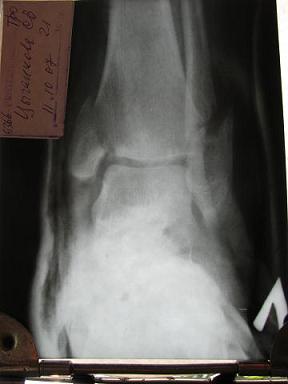

pp3.JPG

в гипсе, все что смогли сделать в Феодосии

pp3.JPG (18.3 КБ) Просмотров: 7159